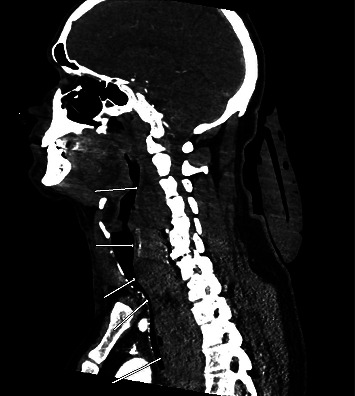

本病例讨论的是一名 47 岁的高加索男性,既往病史包括血脂异常、胃食管反流病、既往颈椎手术和焦虑症,在进行 C5-6 颈椎融合术后出现颈部血肿。医生紧急进行了颈部探查并清除了血肿,恢复了通气。患者被转入重症监护室,术后第 5 天拔管,伤口稳定,无残留出血。三周后复诊时,患者情况良好,胸片显示无渗出或血肿。本报告阐明了颈椎手术后颈部血肿并发症的急性临床症状及其与潜在病因的相关性、后续处理和结果所带来的挑战。

This case study discusses a 47-year-old Caucasian male with a past medical history of dyslipidemia, gastroesophageal reflux disease, previous cervical spine surgery, and anxiety who developed a neck hematoma postrevision of a C5-6 cervical spine fusion. Emergent neck exploration and evacuation of the hematoma were performed, and ventilation was restored. The patient was transferred to the intensive care unit and extubated on postoperative day 5 with a stable wound and no residual bleeding. At the 3-week follow-up appointment, the patient was noted to be doing well, with a chest radiograph showing no effusion or hematoma. This report elucidates the challenges posed by acute clinical symptoms and their correlation with the underlying cause, as well as the subsequent management and outcomes of a neck hematoma complication following cervical spine surgery.